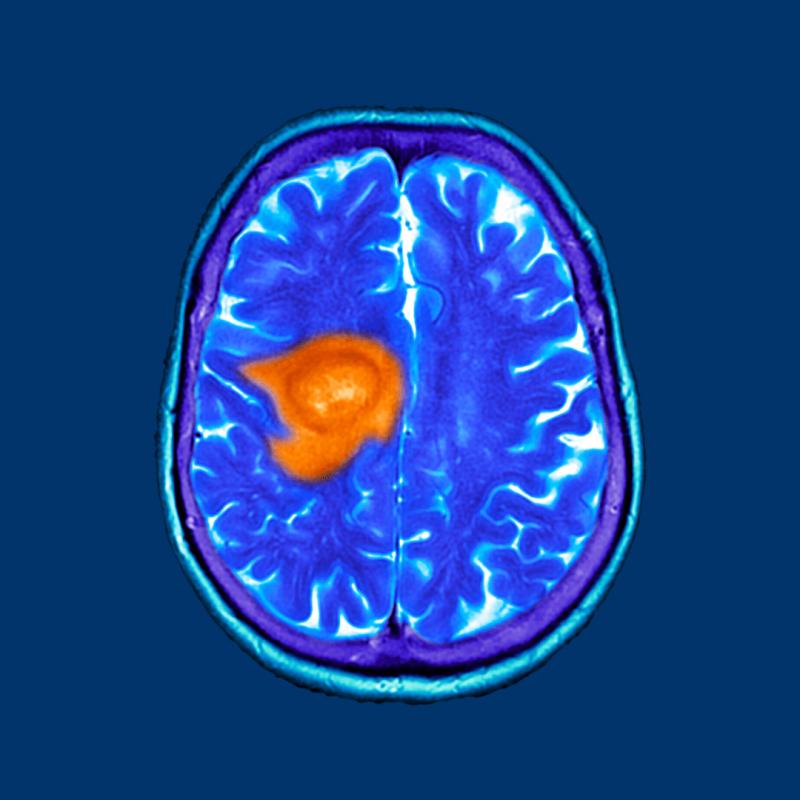

In recent years, complementary and alternative therapies have gained increasing attention in the fight against cancer. One such therapy generating interest in the medical community is Hyperbaric Oxygen Treatment for Cancer. Though traditionally used for conditions such as decompression sickness, non-healing wounds, and carbon monoxide poisoning, hyperbaric oxygen therapy (HBOT) is now being explored for its potential benefits in oncology.

The exploration of Hyperbaric Oxygen Treatment for Cancer stems from a deeper understanding of how tumors behave in low-oxygen (hypoxic) environments. Many cancerous tumors have poor blood supply, which limits oxygen availability and can make them more resistant to traditional treatments like radiation therapy and chemotherapy.

By flooding the body with oxygen, HBOT may improve the oxygenation of these tumor areas, making them more responsive to other treatments. Some studies suggest that Hyperbaric Oxygen Treatment for Cancer may enhance the effectiveness of radiation therapy — particularly in cases of head, neck, and cervical cancers — by increasing oxygen levels in tumor tissues and boosting radiosensitivity.